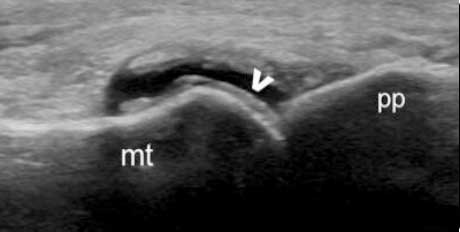

肌骨超声可通过高清影像图判定软骨表面有无出现一条与强回声骨皮质平行的线样强回声,即“双轨征”这一痛风性关节炎特征性表现,判定疾病所属。当尿酸盐粘附并沉积于漂浮的滑膜上时,超声检查可在关节腔内发现漂浮的高亮回声;而当尿酸盐长期沉积于韧带上时,在超声中即显示条带状的略高回声(韧带)中出现高回声点、高回声带或高回声团块(尿酸盐),从而判断痛风病情处于哪一时期。

超声探测结晶呈“双轨征”特性形态